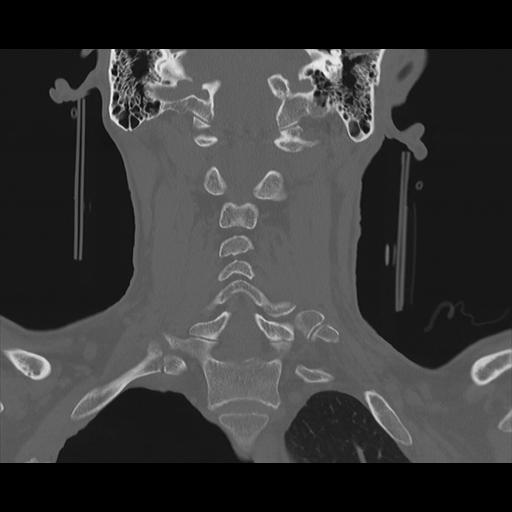

16 HUESO,,Coronal,2.000,HUESO,Coronal,